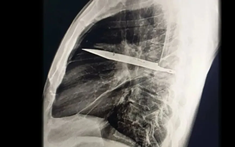

Người đàn ông mang "thứ này" trong lồng ngực suốt 8 năm mà không hề hay biết

Một trường hợp y khoa gây sốc vừa được ghi nhận tại Tanzania: một người đàn ông 44 tuổi đến bệnh viện vì vùng ngực dưới núm vú phải chảy dịch mủ kéo dài 10 ngày. Bệnh nhân không hề sốt, không khó thở, cũng không có biểu hiện đau đớn nào bất thường.